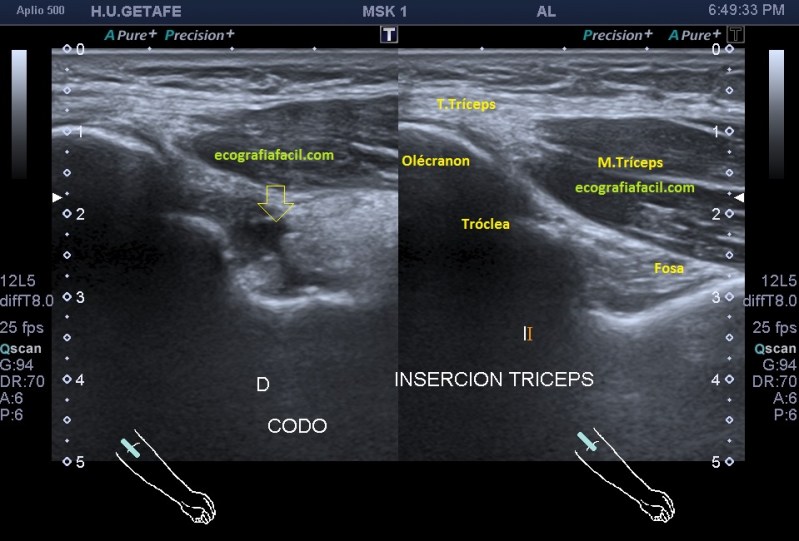

Una de las imágenes más importantes del protocolo de codo es el corte longitudinal de la región posterior para el estudio de la inserción del tríceps en olécranon, pero no solo por esta inserción, me explico…una de las regiones que exploramos en este corte es la fosa olecraniana, que como puedes ver en la imagen es medial y profunda, hiperecogénica en situación normal y donde la presencia de líquido es signo inequívoco de patología locoregional. Además es uno de los objetivos que buscamos en este estudio y por eso siempre documentamos con esta imagen.

La imagen 6 es la misma zona, esta vez explorada en eje corto, la fosa olecraniana tal y como está excavada en la porción distal y posterior del húmero y estudiada en transverso. Los hallazgos corroboran los descritos en la imagen anterior y estudiada en eje largo.